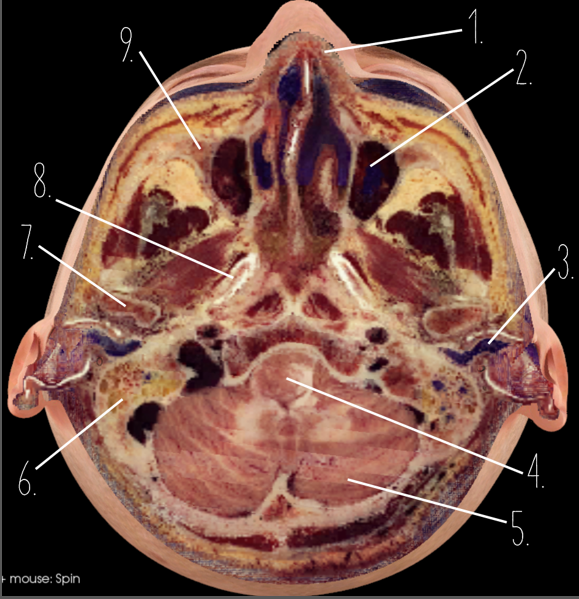

1?

Nasal Bone

2?

Maxillary Sinus

3?

External Acoustic Meatus

4?

Pons

5?

Cerebellum

6?

Mastoid Air Cells

7?

Mandibular Condyles

8?

Sphenoid Bone

9?

Maxillary Bone